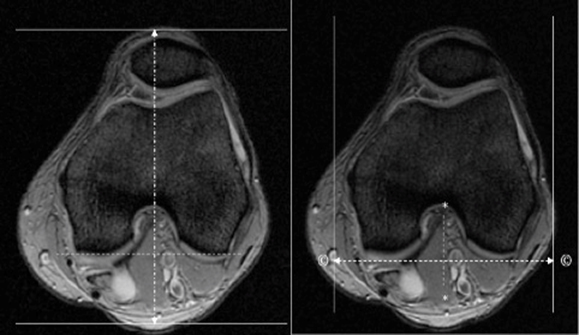

| AXIAL | T2 SPAIR | TSE | 3mm | 0.5mm | SPAIR | 15cm | Cover Infection/Tumor. If hardware is in the area of interest, run STIR instead. |

| AXIAL | T1 | TSE | 3mm | 0.5mm | None | 15cm | Cover Infection/Tumor |